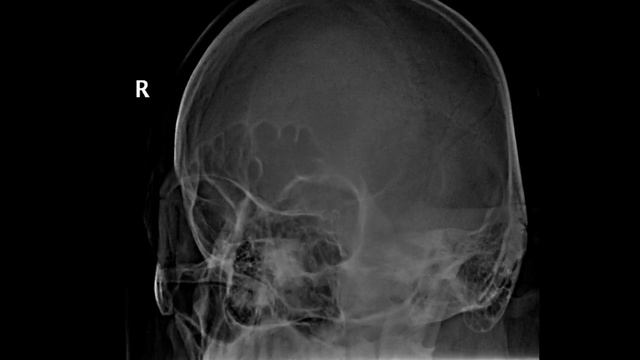

Рентгенография небного шва: Медицинские исследования и диагностика